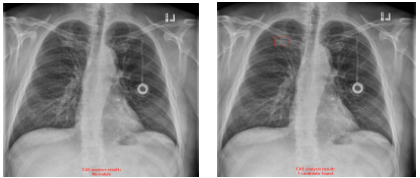

・偽陰性の改善例

旧モデルでは肋骨の重なりに隠れた肺結節候補域を検出できていませんでしたが、新モデルでは検出できています。(5)

※左:旧モデルによる解析結果、右:新モデルによる解析結果